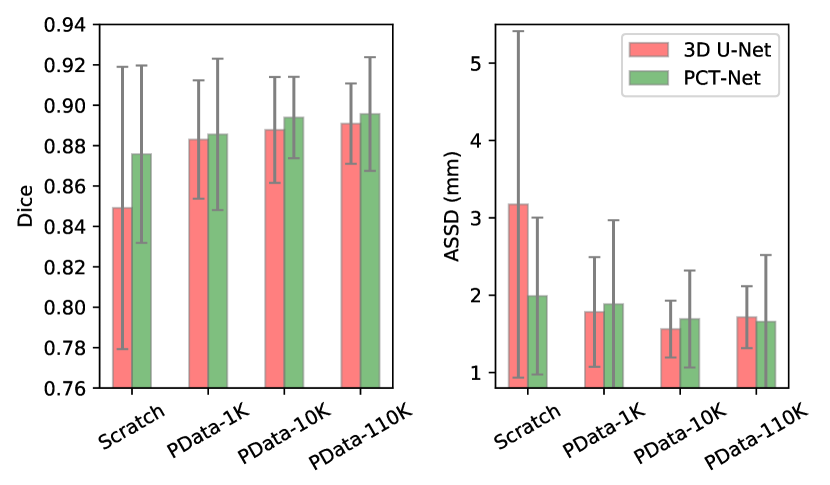

In this section, we conduct ablation studies to investigate the performance of our Volume Fusion with different values and different scales of pretraining data, where 3D UNet [1] and SegTHOR were employed as the segmentation model and downstream segmentation dataset, respectively.

Effect of . To observe the effect of different values on performance of the pretrained model, we set it to 1, 2, 4, 8 and 16 respectively, and pretrained 3D U-Net [1] on PData-1K before training with the SegTHOR dataset. The pretrained models were compared with training from scratch. Quantitative evaluation results on the SegTHOR testing images are shown in Fig. 4. It can be observed that the average Dice value obtained by training from scratch was 84.92%, and all the variants of Volume Fusion outperformed it. Especially, led to an average Dice of 88.08%, and increasing to 2, 4 and 8 further improved the performance, respectively. obtained an average Dice of 87.94%, which was lower than those of the other values, but it was still much better than learning from scratch. In addition, Fig. 4 shows that achieved the lowest average ASSD value of 1.78 mm, compared with 3.17 mm obtained by training from scratch.

Effect of the Scale of Pretraining data. We further compared pretraining with PData-1K, PData-10K and PData-110K using 3D U-Net and PCT-Net, respectively. The results on the SegTHOR dataset when are shown in Fig. 5. For 3D U-Net, PData-1K, PData-10K and PData-110K improved the average Dice from 84.92% to 88.30%, 88.78% and 89.09% respectively. For PCT-Net, training from scratch obtained an average Dice of 87.57%, and PData-1K, PData-10K and PData-110K improved it to 88.56%, 89.39% and 89.56% respectively. The results show that Volume Fusion works on different network structures, and its performance can be improved by leveraging a larger unannotated pretraining dataset.